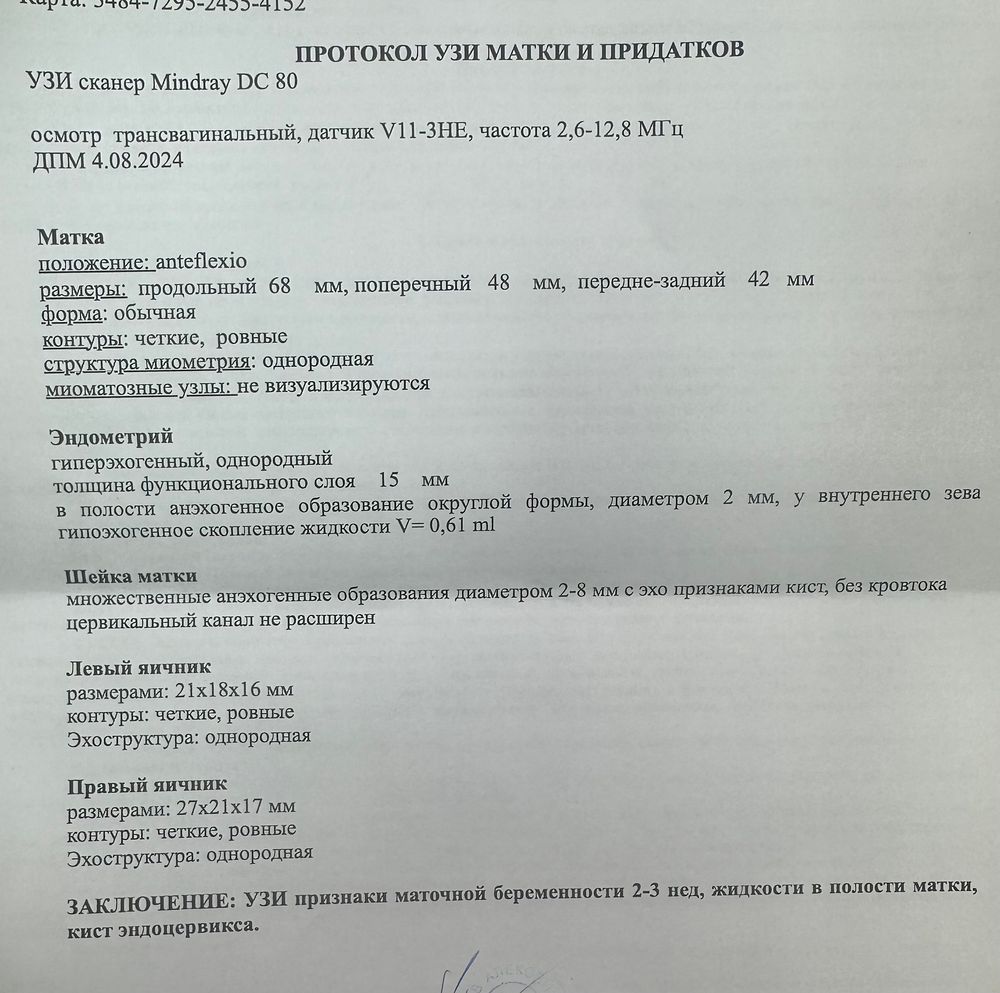

Доброй ночи всем , подскажите пожалуйста, задержка неделя , хгч растет , выделений красных нет , тянет низ живота , срок от овуляции где то 2 н 4 д , узист напугал , сказал похоже на замершую беременность , но это не точно ,сказал жидкость в матке v=0,61 ml, к врачу пока не могу попасть , из за работы, прикрепляю узи, боюсь последствий 😞беременность желанная , что посоветуете ?